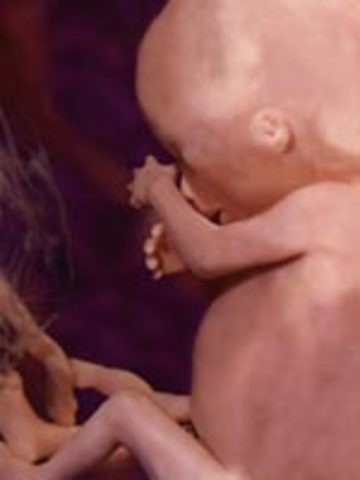

• week 15

week 15

1.baby's legs have grown longer than the arms and the body is now longer than the head

2.Baby is now over 4 inches

• week 16

week 16

1.Fat begins to form underneath skin

2.Baby hears external voices, sleeps and dreams

3.baby has learned to breathe

4.Facial expressions are possible